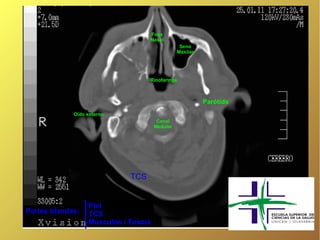

Fosa

Nasal

Seno

Maxilar

Rinofaringe

Parótida

Oído externo

Canal

Medular

TCS

Piel

Partes blandas:   TCS

Músculos / Fascia

Fosa Nasal Seno Maxilar Rinofaringe Parótida Oído externo Canal Medular TCS Piel Partes blandas: TCS Músculos / Fascia